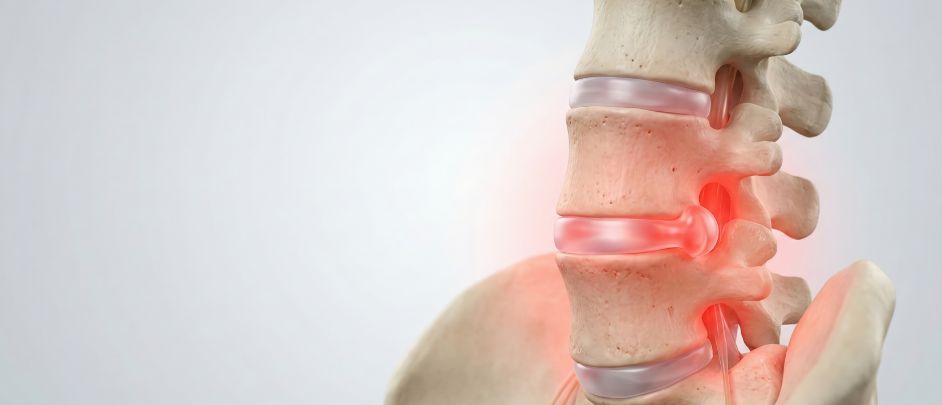

Cirugía de columna mínimamente invasiva

Empleamos técnicas quirúrgicas mínimamente invasivas percutáneas y microscópica (Microdiscectomias).

Patologías de columna

Al menos un 80% de la población presentará alguna vez en la vida un episodio de dolor lumbar. Realizamos una adecuada evaluación para tomar la mejor opción terapéutica.

Tratamiento del dolor crónico cervical y lumbar

Tratamiento del dolor lumbar y cervical crónico, tanto sin o después de cirugía fallida, tras múltiples intentos de varias modalidades de tratamiento conservador (Mediación y fisioterapia).